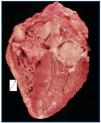

La necropsia demostró un proceso fibrosante sistémico (Figuras 1-4), con afectación de pelvis menor, retroperitoneo, en coraza alrededor de riñones, glándulas suprarrenales y páncreas, abarcando espacio periesplénico y perihepático; y mediastínico, en coraza alrededor de pericardio, arco aórtico y grandes vasos; y paquipleuritis derecha con fibrosis calcificada. Se apreciaron también: pancreatitis crónica fibrosa asociada, atrofia testicular, fenómenos de enfermedad aterombólica, hipertrofia ventricular izdª, y hepatopatía fibrosa crónica, en el contexto de un paciente con arteriosclerosis generalizada severa, con repercusión renal -nefroangiosclerosis bilateral con atrofia renal derecha, encefálica –infarto antiguo quístico izquierdo a nivel de ínsula-, y de colon –colitis isquémica rectosigmoide.

Figura 1.